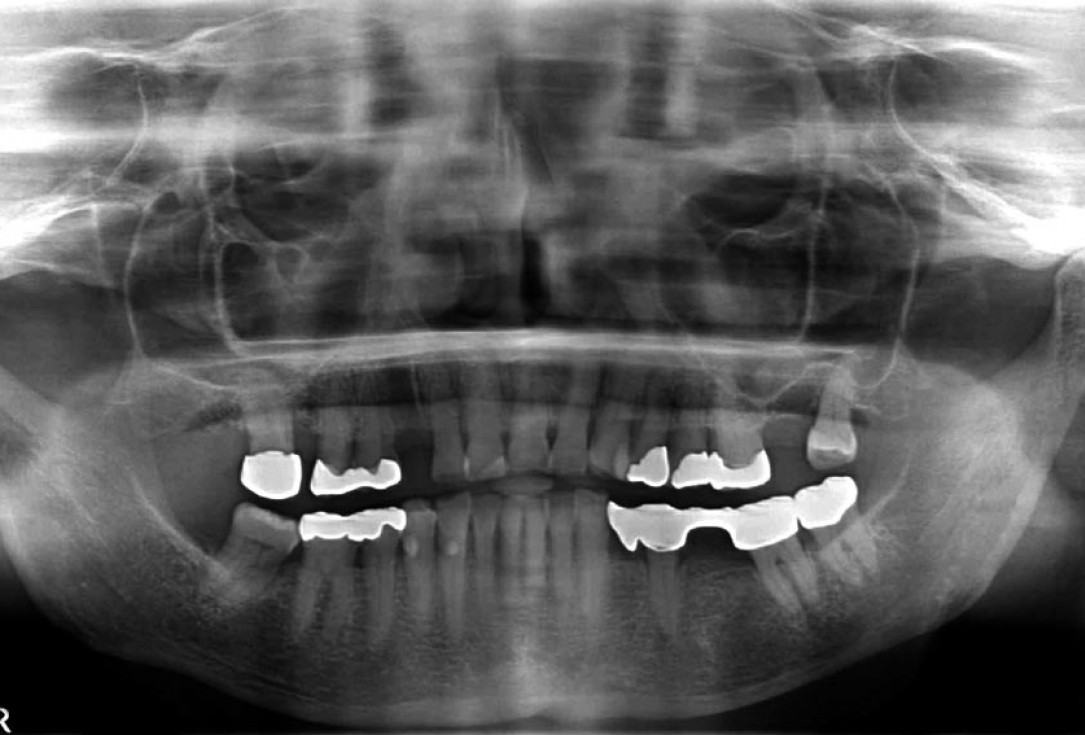

04/12 - Preoperative radiological situation

Block augmentation with maxgraft® in the maxilla - PD Dr. Dr. F. Kloss